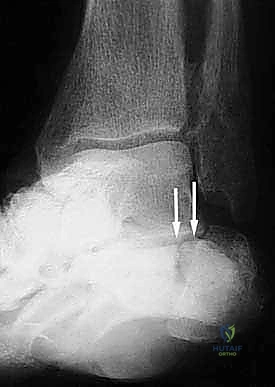

- الأشعة السينية (X-rays) متعددة الزوايا: لتقييم الانهيار العظمي وزوايا الكعب (مثل زاوية بوهلر وزاوية جيسان).

إذا كان الكعب قد فقد ارتفاعه أو انحرف بشكل كبير، يقوم الدكتور هطيف بإجراء قطع دقيق في عظم الكعب لإعادة توجيهه إلى محوره الميكانيكي السليم. يتم استخدام طعوم عظمية (Bone Grafts)—تؤخذ غالباً من حوض المريض أو طعوم صناعية—لرفع الكعب المنهار واستعادة زاوية بوهلر الطبيعية.

- يتم إجراء أشعة سينية للتأكد من بدء التئام العظام والتحام المفصل.